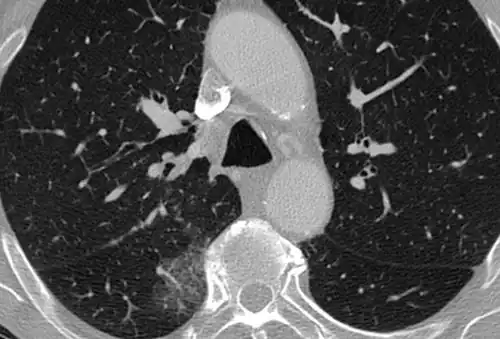

CT image in patient with COVID-19 showing bilateral ground-glass opacities at the periphery of both lungs.

Ground-glass opacity is among the most common imaging findings in patients with confirmed COVID-19.[16][17] One systematic review found that among patients with COVID-19 and abnormal lung findings on CT, greater than 80% had GGOs, with greater than 50% having mixed GGOs and consolidation.[16] GGOs with mixed consolidation has most often been found in elderly populations.[18] Several studies have described a pattern among initial, intermediate, and hospital discharge imaging findings in the disease course of COVID-19. Most commonly, initial CT imaging reveals bilateral GGOs at the periphery of the lungs. During initial stages, this is most often found in the lower lobes, although involvement of the upper lobes and right middle lobe has also been reported early in the disease course.[16][18] This is in contrast to the two similar coronaviruses, SARS and MERS, which more commonly involve only one lung on initial imaging.[19][20] As the COVID-19 infection progresses, GGOs typically become more diffuse and often progress to consolidation.[11][18] This is sometimes accompanied by the development of a crazy paving pattern and interlobular septal thickening.[18] In many cases the most severe pulmonary CT abnormalities occurred within 2 weeks after symptoms began.[17] At this point, many individuals begin showing resolution of consolidation and GGOs as symptoms improve. However, some patients have worsening symptoms and imaging findings, with further increase in septal thickening, GGOs, and consolidation. These patients may develop lung "white-out" with progression to acute respiratory distress syndrome (ARDS) requiring treatment escalation.[17][21]